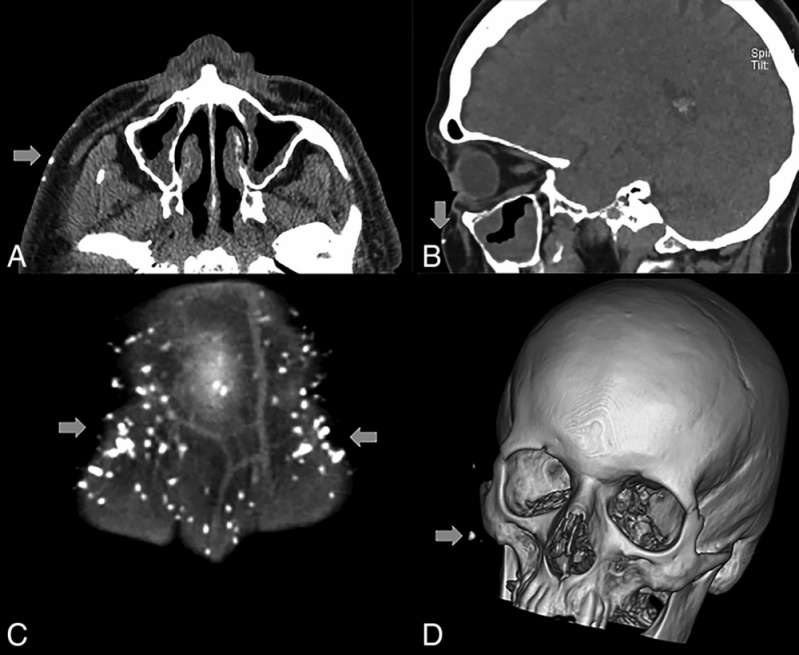

Exame de Imagem Tomografia do Crânio

Exame de Imagem Tomografia do Crânio

Exame de Imagem Tomografia do Crânio

Medicom ExamesUm exame de imagem é diferente dos exames endoscópicos, onde são inseridos tubos flexíveis com luz e lentes ou uma câmera de vídeo, dentro do corpo... Cotar Agora Saiba Mais